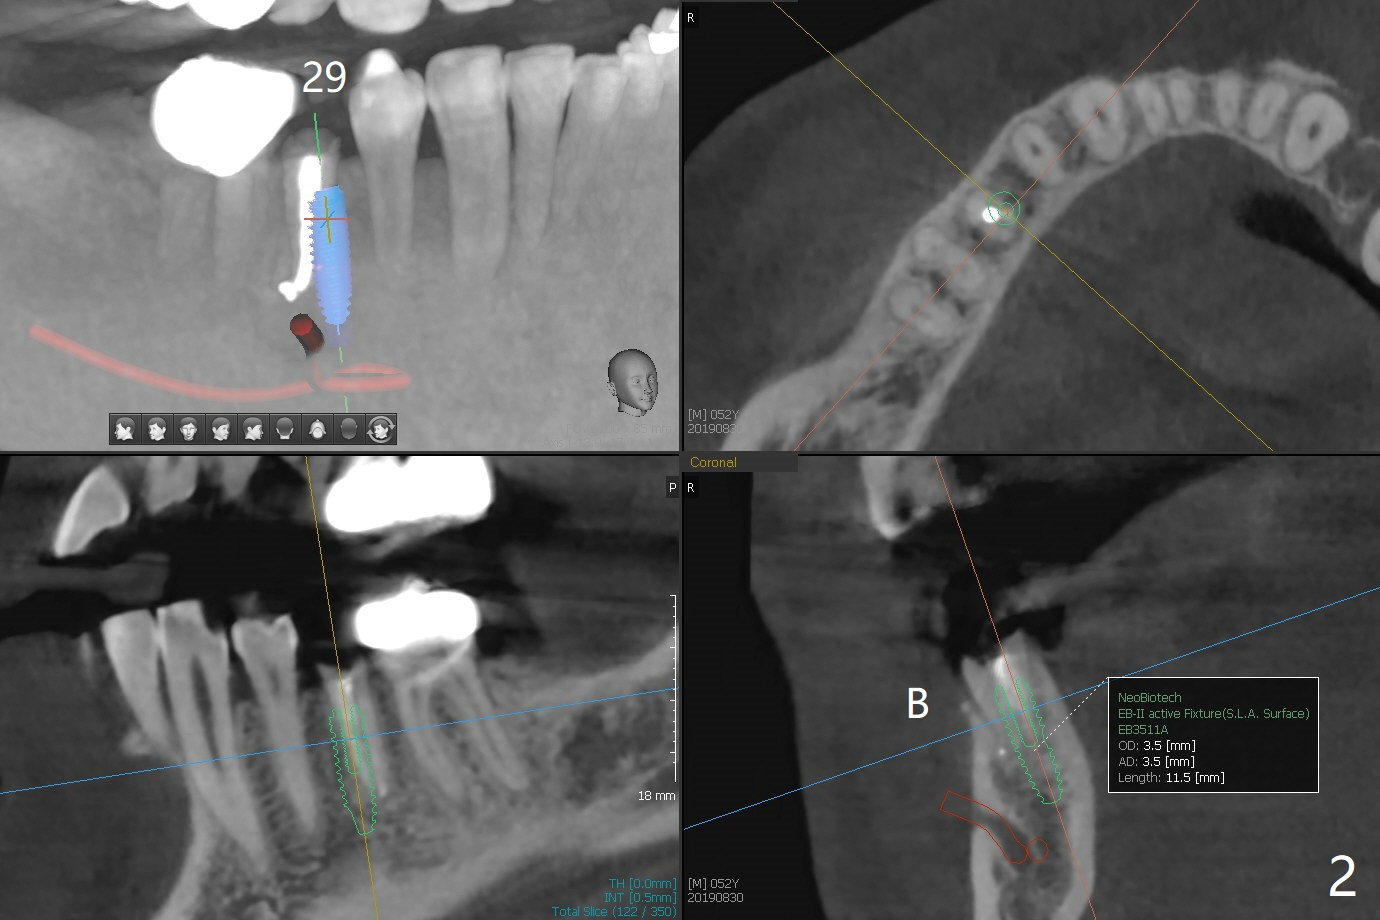

A 52-year-old man chooses to take care of the teeth #21 and 29 first due to finance (Fig.1). The implant diameter should not be too large because of the moderate mesiodistal space (Fig.2,3). Since the buccal plate of #21 is indistinct (socket shield will be done), the implant should be a little more lingually placed than the design in Fig.3, although the implant placement level seems to be acceptable. Socket shield seems to be necessary.